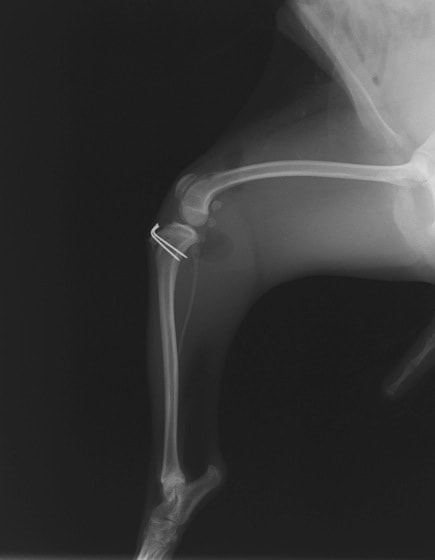

■ 症例24 キャバリア 7か月

左右膝蓋骨内方脱臼(左:グレードⅣ 右:グレードⅢ)

以前から左右後肢の跛行が認められ、整形外科学的検査・レントゲン検査により左右の膝蓋骨脱臼が認められた。症状が重度である左膝の膝蓋骨脱臼整復術を行った。外科手技は縫工筋及び内側広筋の解放、脛骨粗面の外側転位、滑車ブロック形造溝術、内外側関節方の縫縮を実施した。術後一か月時点で、左の膝蓋骨は安定しており経過は良好である。

本症例は成長期における重度の膝蓋骨脱臼であり、術後の再発の可能性もあるため、経過をしっかりと観察していく必要がある。また、今回手術を実施していない右膝に関しても経過を観察し、手術を検討していくこととする。